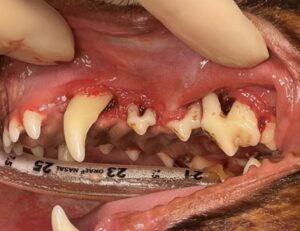

当院で治療した症例

軽度の症例

処置前